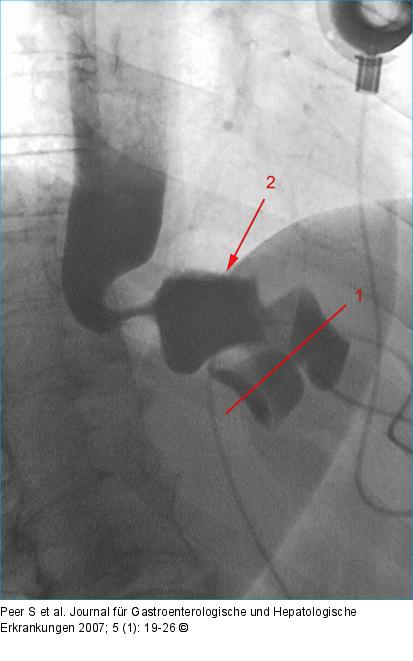

Abbildung 3: SAGB Normalbefund nach SAGB (postoperative Untersuchung mit wasserlöslichem Kontrastmittel): Korrekte Bandachse des gering gefüllten (standardisierte Füllung!) Bandes (1), kleiner, normaler Magenpouch mit Luft-Kontrastmittel-Spiegel (2). |

Normalbefund nach SAGB (postoperative Untersuchung mit wasserlöslichem Kontrastmittel): Korrekte Bandachse des gering gefüllten (standardisierte Füllung!) Bandes (1), kleiner, normaler Magenpouch mit Luft-Kontrastmittel-Spiegel (2). |